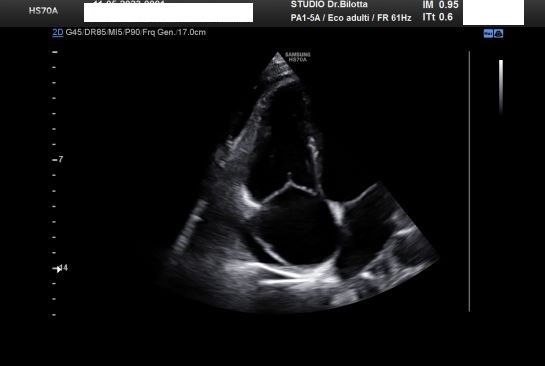

Diploma di maturità classica. Laurea in Medicina e Chirurgia con Lode a 26 anni. Specialista in Oncologia Generale Diagnostica e Preventiva con Lode a 31 anni. Specialista in Malattie Cardiovascolari a 36 anni. Medico generalista dal 1990 poi ospedaliero per trent'anni dal 1993 al 2022 nel corso dei quali ho refertato oltre 100 mila tracciati elettrocardiografici, effettuato oltre 30 mila consulenze specialistiche, praticato circa 10 mila esami ecocardiografici, condotto oltre 2 mila test ergometrici sia su cicloergometro che su treadmill, visionato circa 1500 esami Holter Ecg e ABP ( Ambulatory Blood Pressure ) occupandomi prevalentemente di prevenzione cardiovascolare, ipertensione arteriosa, cardiopatia ischemica, valvulopatie. Dal 2023 ho deciso di trasferire le mie competenze nella libera professione presso il mio studio privato che è stato allestito in linea alle moderne esigenze tecnologiche. Metodiche diagnostiche attualmente praticate: Elettrocardiografia a riposo, Ecocardiografia mono-bidimensionale, PW, CW, Colordoppler tridimensionale, GLS Strain Speckle tracking, Monitoraggio Holter Pressorio delle 24 ore, Monitoraggio Holter ECG 12 canali dinamico delle 24 ore.

Foto e video